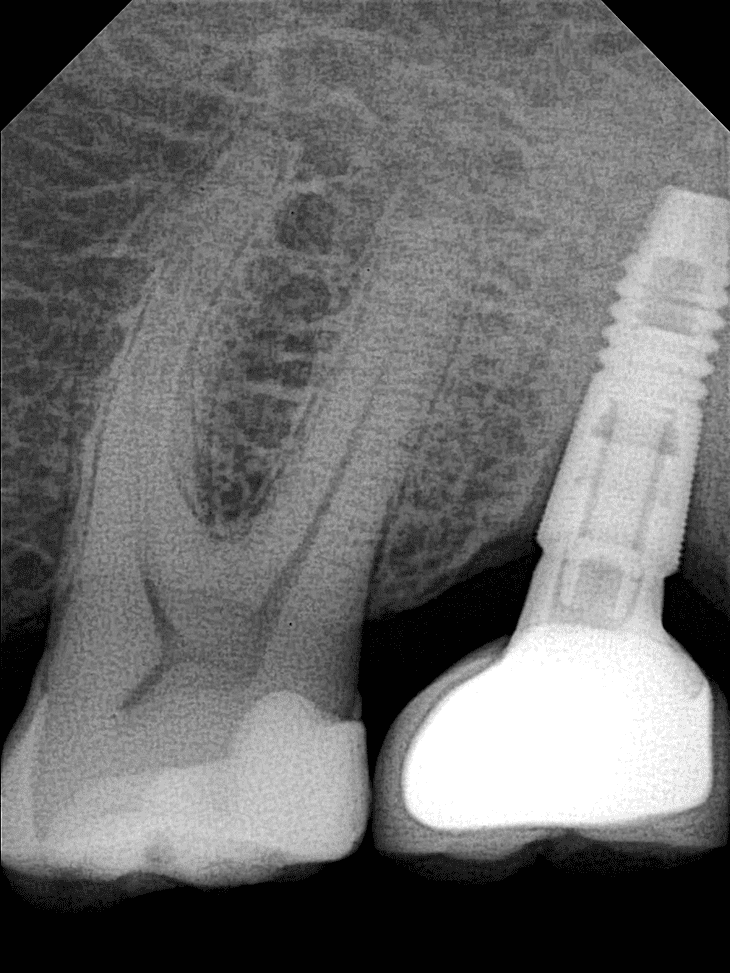

OPTEO Sensor – Klinische Bildgalerie

Ultra-HD Bildqualität – 18,5 Mikron Präzision Außergewöhnlich klare und detaillierte intraorale Bildgebung.

- Endodontie: Verbesserte Präzision für erfolgreiche Wurzelkanalbehandlungen.

- Implantat- & Prothesenchirurgie: Optimierte Planung und Nachsorge.